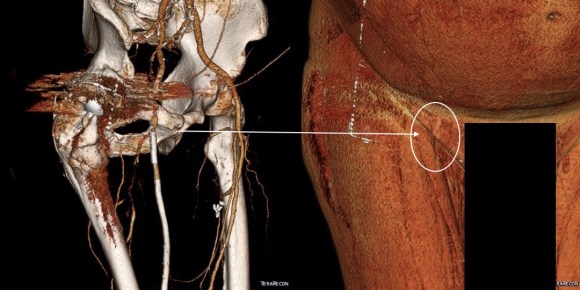

The patient came back in followup -it has been 4 years since his infection was repaired. He was complaining of short distance claudication. His wound healed well and remains closed. CTA shows along with his short segment SFA occlusion which we will treat, a widely patent R. EIA (below).

The remote endarterectomy of the external iliac artery remains patent. Compare this to the preop CTA which I found and wasn’t available when I posted this case originally:

The chronically occluded EIA can be readily seen. The artery shown in the current CTA is that recanalized artery.

CTA (pictured above and below) showed a 5.1cm infrarenal AAA with an hourglass shaped neck with moderate atherosclerosis in the neck, an occluded left common iliac artery with external iliac artery reconstitution via internal iliac artery collaterals, and a right external iliac artery occlusion with common femoral artery reconstitution. There was calcified right common femoral artery plaque.